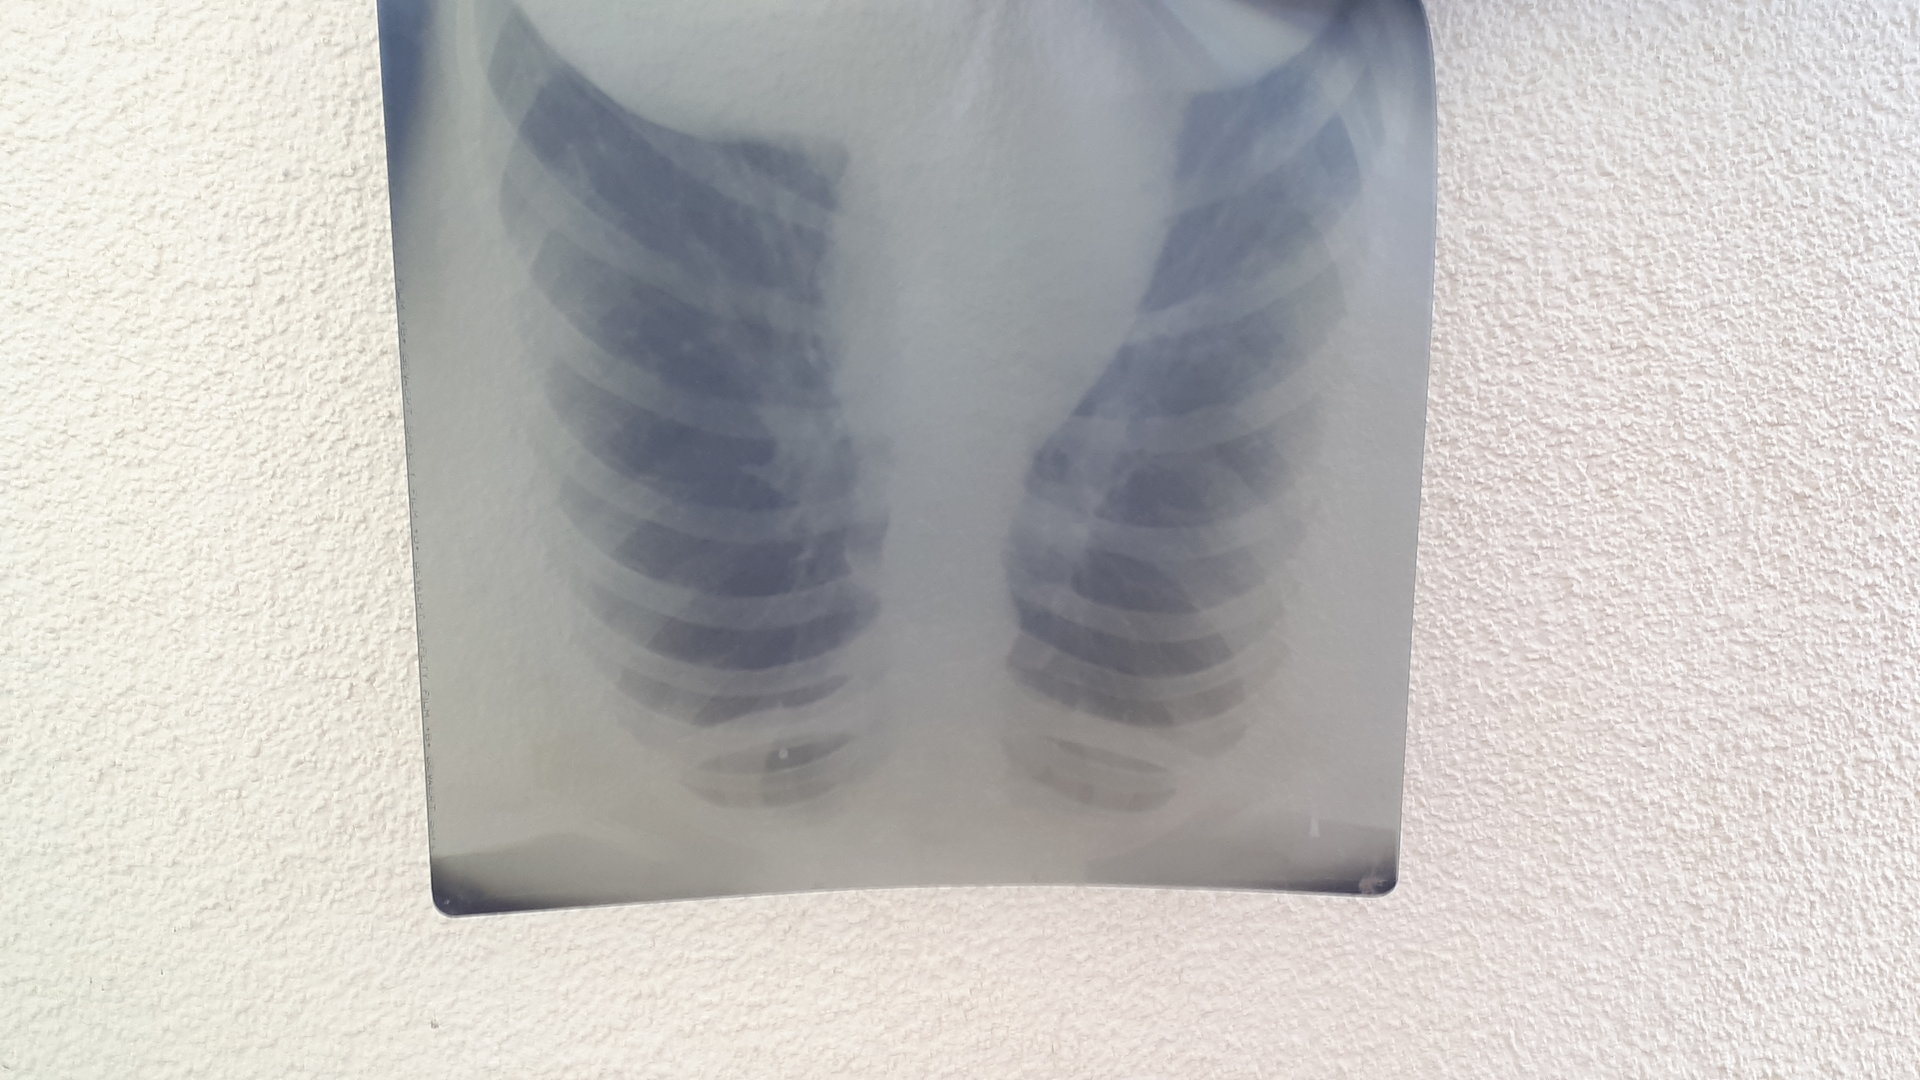

Die ganze Entwicklung in den Naturwissenschaften wäre nicht möglich gewesen, wenn nicht Menschen immer weiter gefragt hätten, um die Naturgesetze zu verstehen. Fortschritte in Physik, Chemie, Biologie und Medizin wären ohne diese Forschungen nicht passiert. Einer dieser Forscher war Wilhelm Conrad Röntgen, der am 23. März 1845 in Remscheid geboren wurde. Seine erste Röntgenaufnahme fertigte er, vor 125 Jahren, 1895, von der Hand seiner Frau Bertha an. Zu der Zeit ist er Professor in Würzburg. Heute ist der historische Laborraum in eine Gedächtnisstätte umgewandelt. (Link zur Homepage: wilhelmconradroentgen.de) In der Medizin eröffnet diese Entdeckung phänomenale Möglichkeiten. Man kann Knochenbrüche erkennen, Fremdkörper aufspüren, Verformungen erkennen und so die Behandlung der Patienten verbessern.

Allein im medizinischen Bereich werden heute 132 Millionen Anwendungen in Deutschland vorgenommen. Aber auch in der Physik, Chemie, Astronomie und der Materialprüfung, vor allem im Baugewerbe sind die Röntgenstrahlen unverzichtbar. 1901 erhielt Wilhelm Conrad Röntgen den 1. Physik-Nobelpreis für seine Entdeckung. Marie Curie konstruierte später im 1. Weltkrieg einen fahrbaren Röntgenapparat, um die Soldaten gleich vor Ort zu röntgen. Aber wie häufig bei neuer Technik, sie ist ein Segen. Die Gefahren, die damit verbunden sein können, treten erst später auf. Die Schäden, die durch Röntgenstrahlen entstehen, wurden erst mit der Zeit erkennbar und vielleicht erinnern Sie sich auch noch an den Kauf von Schuhen. Im Schuhgeschäft wurde der Fuß im Schuh geröntgt, ob der Schuh passte. Heute undenkbar.